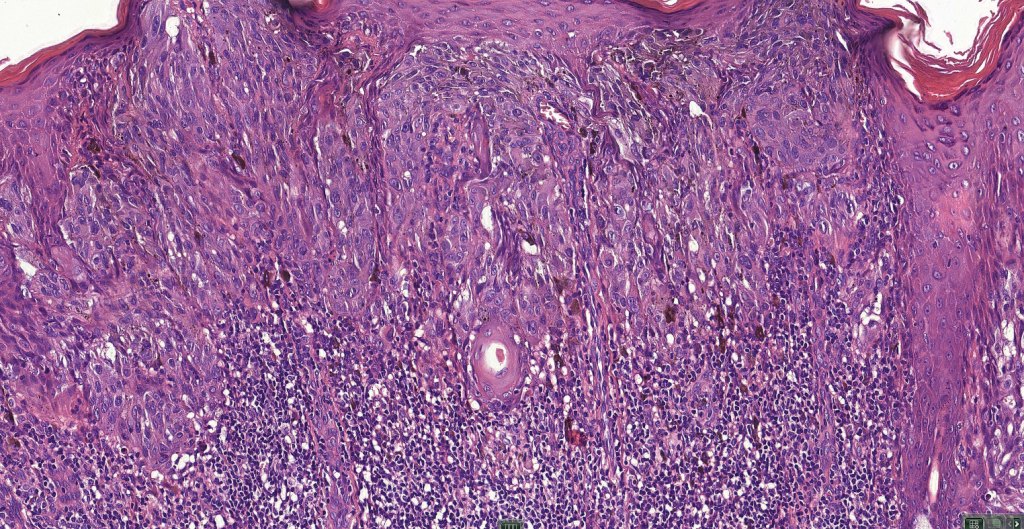

•Junctional nests often vertically orientated, dyscohesive with a surrounding retraction artifact

•Pleomorphism is almost invariable but affects all of the population to the same extent i.e., the cells & nuclei all look very much the same

•Spindle cell nests often display a “raining down” growth pattern

•Spindle cells have abundant cytoplasm and vesicular nuclei with small nucleoli

•Epithelioid cell variants often show greater pleomorphism and cells can frequently appear bizarre with abundant, sometimes ground glass cytoplasm and large vesicular nuclei with prominent eosinophilic nucleoli, multinucleate cells are often seen

•Intracytoplasmic pseudoinclusions commonly present in epithelioid cells

•Mitoses can brisk in younger patients and should not be taken as indicating melanoma

•Mitoses are restricted to the superficial aspect on the nevus and are never atypical

•Kamino bodies (often multiple) are a characteristic feature